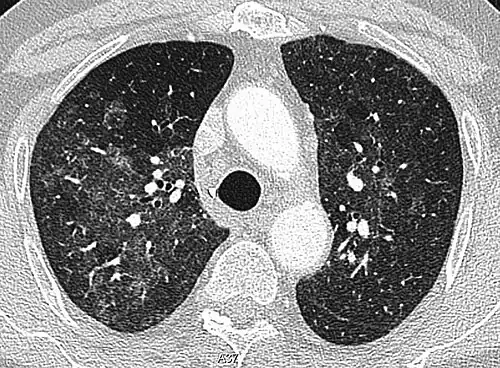

CT image in patient with COVID-19 showing bilateral ground-glass opacities at the periphery of both lungs.

Ground-glass opacity is among the most common imaging findings in patients with confirmed COVID-19.[16][17] One systematic review found that among patients with COVID-19 and abnormal lung findings on CT, greater than 80% had GGOs, with greater than 50% having mixed GGOs and consolidation.[16] GGOs with mixed consolidation has most often been found in elderly populations.[18] Several studies have described a pattern among initial, intermediate, and hospital discharge imaging findings in the disease course of COVID-19. Most commonly, initial CT imaging reveals bilateral GGOs at the periphery of the lungs. During initial stages, this is most often found in the lower lobes, although involvement of the upper lobes and right middle lobe has also been reported early in the disease course.[16][18] This is in contrast to the two similar coronaviruses, SARS and MERS, which more commonly involve only one lung on initial imaging.[19][20] As the COVID-19 infection progresses, GGOs typically become more diffuse and often progress to consolidation.[11][18] This is sometimes accompanied by the development of a crazy paving pattern and interlobular septal thickening.[18] In many cases the most severe pulmonary CT abnormalities occurred within 2 weeks after symptoms began.[17] At this point, many individuals begin showing resolution of consolidation and GGOs as symptoms improve. However, some patients have worsening symptoms and imaging findings, with further increase in septal thickening, GGOs, and consolidation. These patients may develop lung "white-out" with progression to acute respiratory distress syndrome (ARDS) requiring treatment escalation.[17][21]

Preliminary reports have shown many patients have residual GGOs at time of discharge from the hospital. Due to the novelty of COVID-19, large studies investigating the long-term pulmonary CT changes have yet to be completed. However, long-term pulmonary changes have been seen in patients after recovery from SARS and MERS, suggesting the possibility of similar long-term complications in patients who have recovered from acute COVID-19 infection.[22]